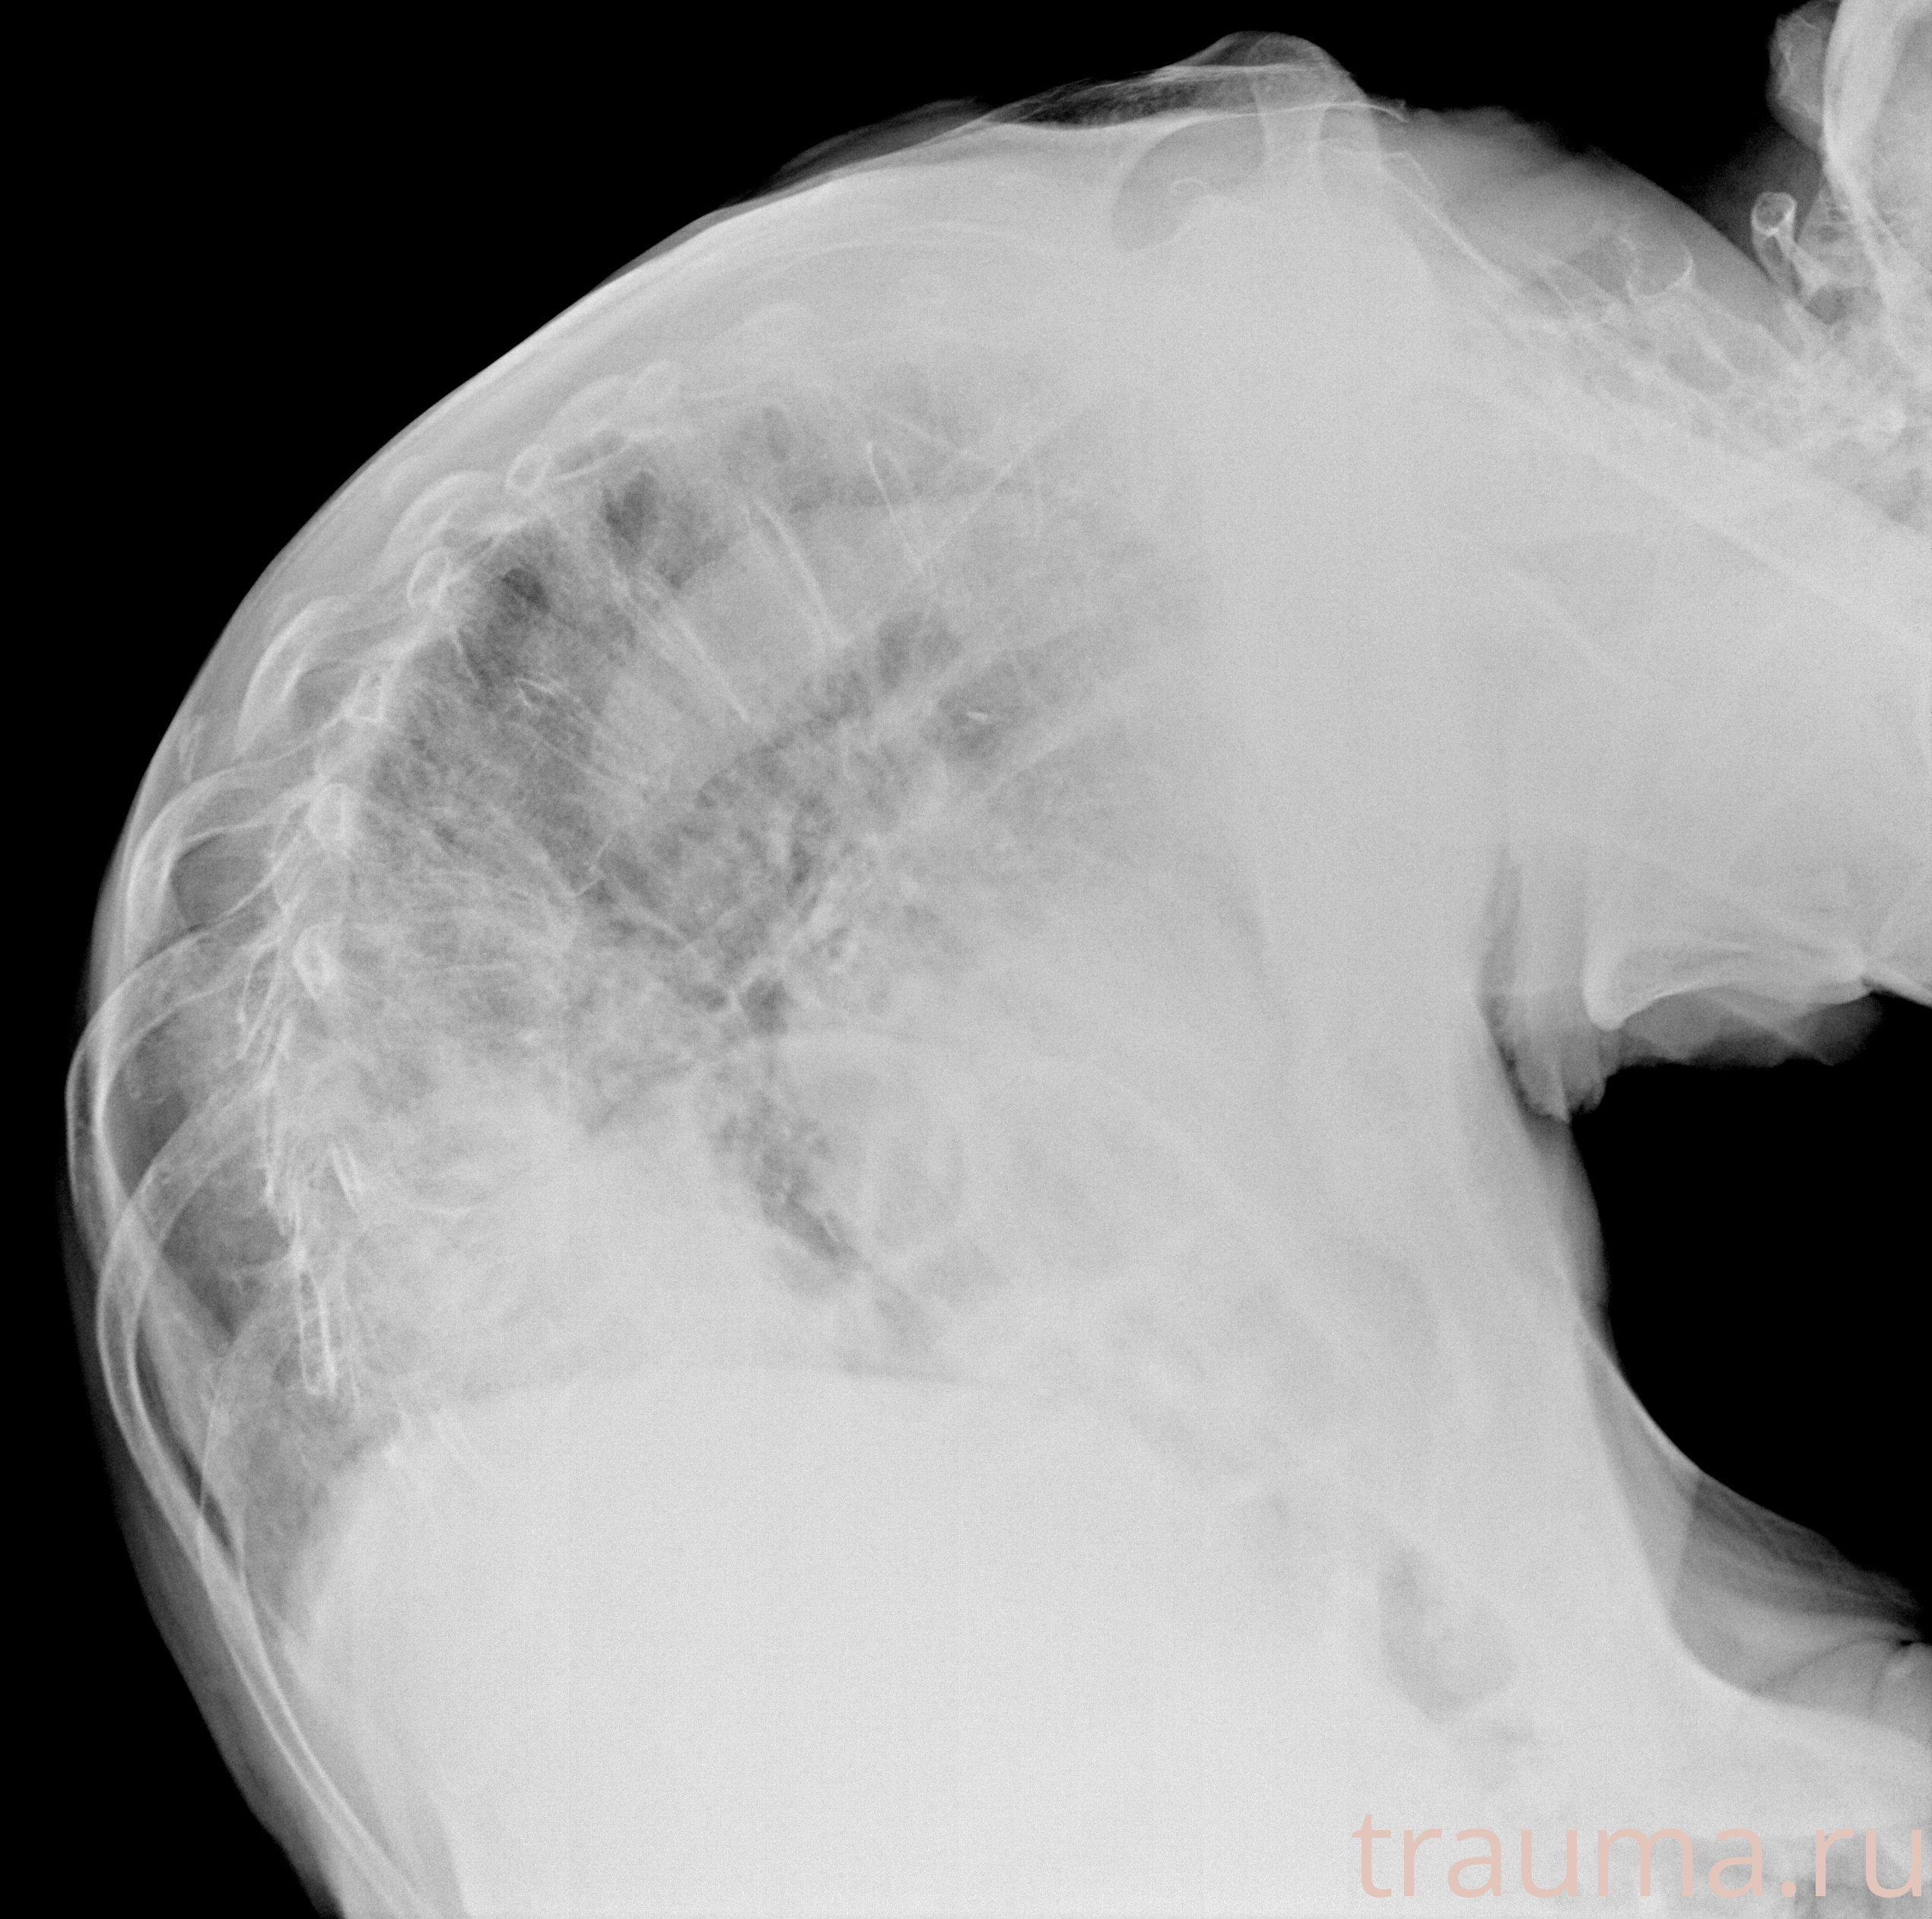

Рентгенограммы

Рентген на дому: по вашему адресу приезжает врач-рентгенолог, травматолог-ортопед с мобильным рентгеновским аппаратом, проводит диагностику травмы или заболевания, делает необходимые рентгенограммы, дает рекомендации по дальнейшему лечению. Получить качественные снимки в домашних условиях возможно благодаря уникальной методике, разработанной МосРентген Центром для института  Склифосовского

при переломе шейки бедра и пневмонии от компании МосРентген Центр - партнера Института имени Склифосовского